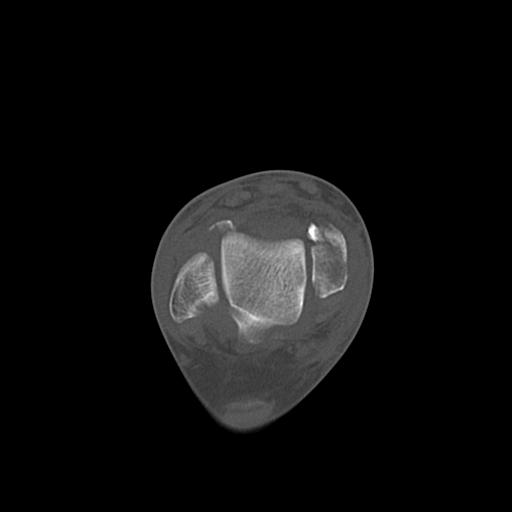

49554 3/13 膝 4R 3/16 4R 1/18 2R 78歳男性 膝蓋骨骨折